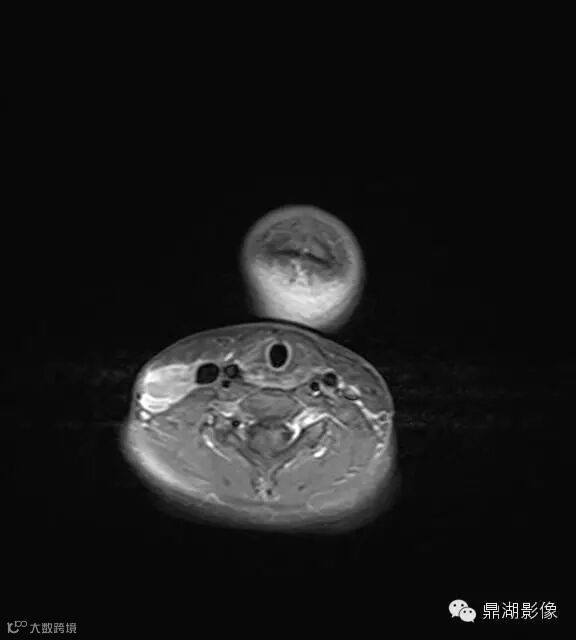

上海儿童医院韩燕乔教授诊断:考虑淋巴结炎 ,可见杯状分层,液液平

淋巴结核:多融合成团,呈花环状,边缘强化,淋巴结内见到斑点状钙化有助结核的诊断。

猫抓病性淋巴结炎:不少医生诊断为猫爪病,该病确实很接近。均为炎性改变,脓肿、坏死形成时,虽呈边缘强化特点,但多个淋巴结间界限清楚,无融合改变,内也无斑点状钙化。